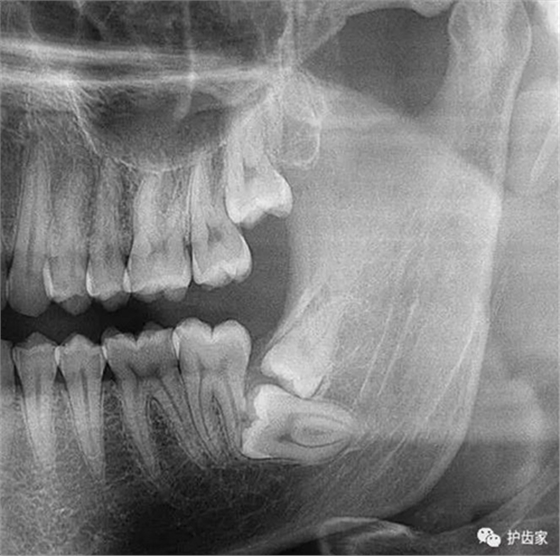

根神經(jīng)線位置千變?nèi)f化,有些離智齒牙根很遠(yuǎn),有些很近,有些甚至穿過智齒根部。

拍片是為了了解智齒周圍情況,也是為了了解智齒結(jié)構(gòu),牙根結(jié)構(gòu)千變?nèi)f化,有可能是融合成一個(gè)根,也可能是八爪根。不同牙根不同位置及方向,只有通過拍片來確認(rèn)。

拍片也為了了解下頜神經(jīng)與智齒的關(guān)系,一般離得近,有醫(yī)療風(fēng)險(xiǎn)的,基本沒有醫(yī)生愿意拔,現(xiàn)在沒人為了幾百元,賠上自己的職業(yè)生涯。誰都怕拔智齒,敲打智齒,一不小心,碰到神經(jīng),就攤上大事了。有理都說不清。

通過拍片可以了解牙齒本身:生長方向,牙根數(shù)目,牙根是否彎曲,膨大等。

與重要解剖結(jié)構(gòu)的位置關(guān)系:如上頜磨牙與上頜竇的關(guān)系;下頜磨牙與下頜神經(jīng)管的關(guān)系;兒童在混合牙列期恒牙與乳牙胚的關(guān)系等??梢詼p少拔牙的風(fēng)險(xiǎn)。